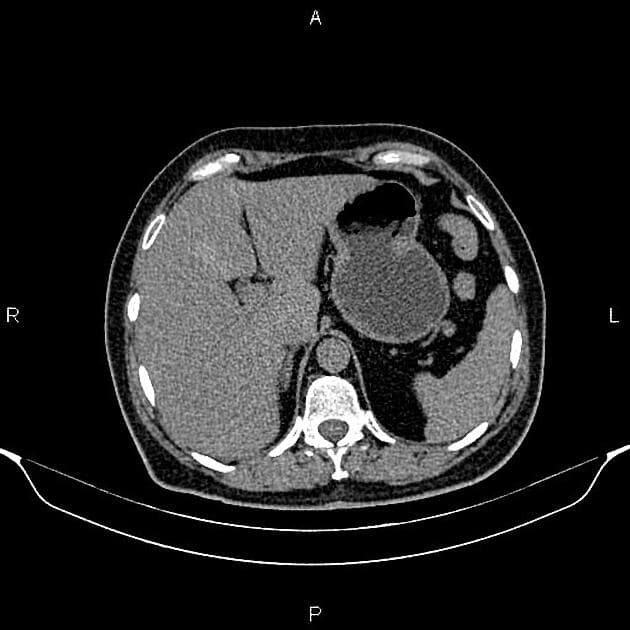

Axial C+ delayed

- Ghi nhận khối tổn thương bán lồi ra ngoài (exophytic), dị tỷ trọng (hetero-dense), kích thước 133 × 114 × 122 mm, ở mặt trước thận trái. Sau tiêm thuốc cản quang, khối cho thấy ngấm thuốc không đồng nhất (heterogeneous enhancement) với vùng hoại tử trung tâm (central necrosis) rộng lớn. Không có dấu hiệu xâm lấn tại chỗ và không có lan rộng vào mạch máu.

Bệnh nhân đã được thực hiện phẫu thuật cắt bỏ thận trái, và kết quả giải phẫu bệnh học (histopathology) xác nhận ung thư biểu mô tế bào thận (renal cell carcinoma) với thành phần hoại tử (necrosis) lớn.

Cần lưu ý rằng hoại tử trung tâm (central necrosis) là tổn thương thường gặp trong các khối ung thư biểu mô tế bào thận (renal cell carcinoma) lớn và có thể bắt chước khối nang thận phân loại Bosniak IV. Do đó, theo nguyên tắc, nếu thể tích thành phần đặc ngấm thuốc (enhancing solid component) của một tổn thương nang thận vượt quá 25% tổng thể tích khối, thì không nên áp dụng phân loại Bosniak, mà thay vào đó nên xếp khối này là khối đặc thận (solid renal mass) kèm theo thay đổi nang/hoại tử (cystic/necrotic changes); bởi vì tiên lượng của ung thư biểu mô tế bào thận (renal cell carcinoma) dạng đặc có thay đổi nang/hoại tử (cystic/necrotic changes) thường xấu hơn so với ung thư biểu mô tế bào thận (renal cell carcinoma) phát triển từ khối nang thận Bosniak loại IV¹.